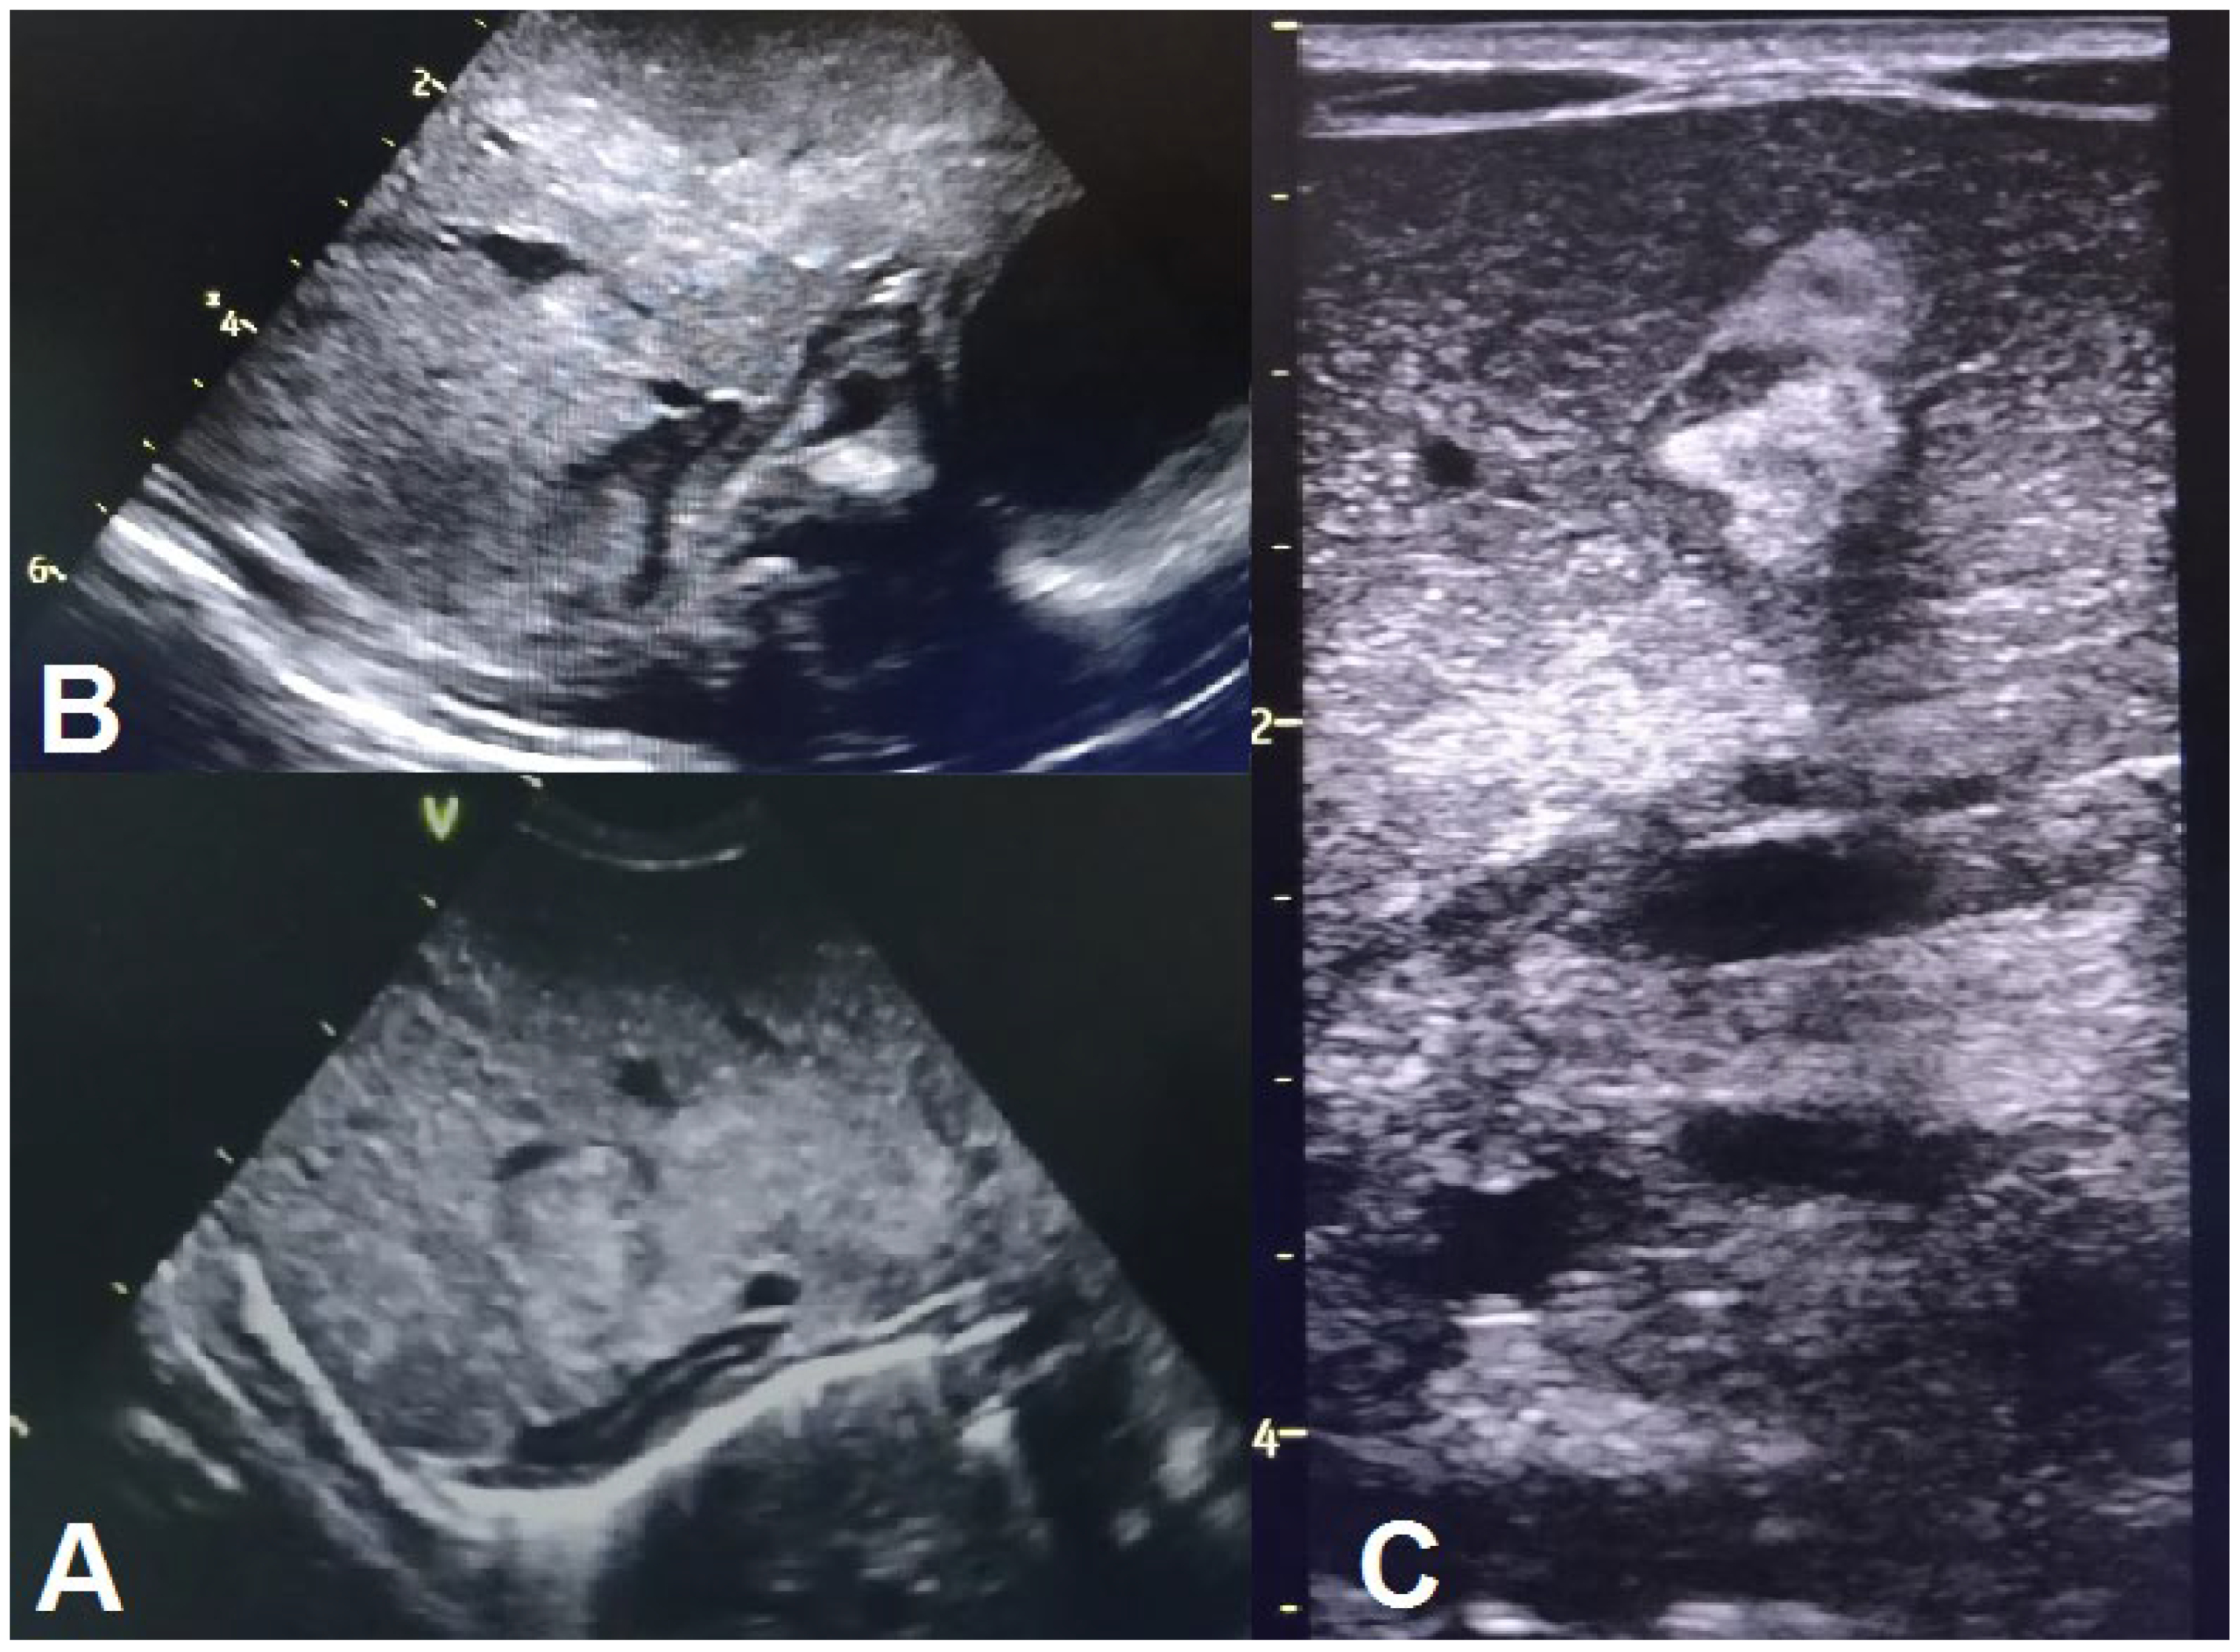

| Thoraco-abdominal radiography | No lung or abdominal involvement | Suggestive of respiratory distress syndrome due to surfactant deficiency on DOL6 0; pronounced reticular, micronodular bilateral lung interstitium on DOL6 5 | |||||||||||

| Abdominal ultrasound | Suspected neuroblastoma on DOL6 1; abdominal situs inversus on DOL6 2; no abdominal parenchymal involvement on DOL6 2 and 10 | Gross, inhomogenous, patchy echogenic areas disseminated, almost throughout the entire liver on DOL6 9; fine granular echogenic areas limited to the fourth hepatic segment by DOL6 14; normal hepatic ultrasound structure on DOL6 45 | |||||||||||